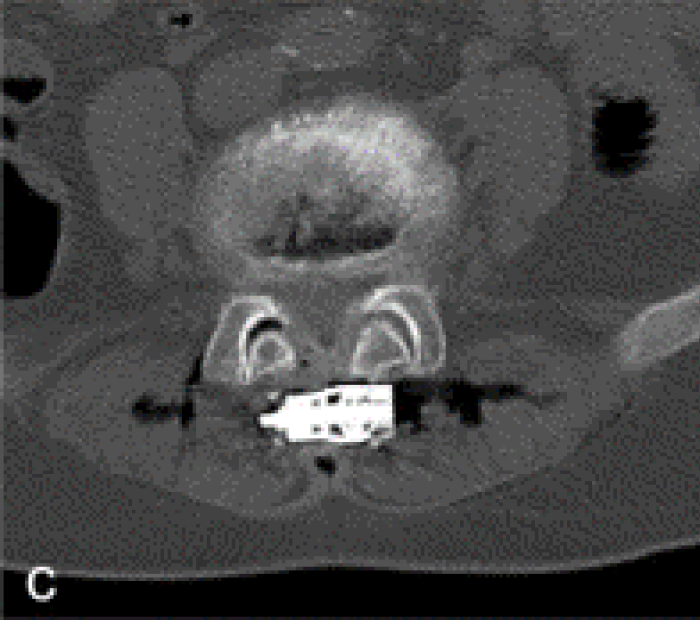

治療結果c

b~d:L4/L5の棘突起間にスペーサーを挿入したことによる、棘突起間隔の拡大と黄色靭帯肥厚の軽減が認められる治療後のCT画像

軽減が認められる治療後のCT画像